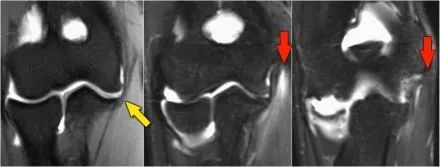

下面的图我们看到UCL的两个连续冠状图像。在近端部分(箭头)看到一些高信号是正常的。注意它是如何牢固地附着在崇高的结节上并将其与下一个图像进行比较。

请记住,UCL应该非常紧密地附着在崇高的结节上。在下面这种情况下它没有,所以即使在这两个图像上你也可以看出它有完全的撕裂。请注意,崇高结节中存在一些骨髓水肿。